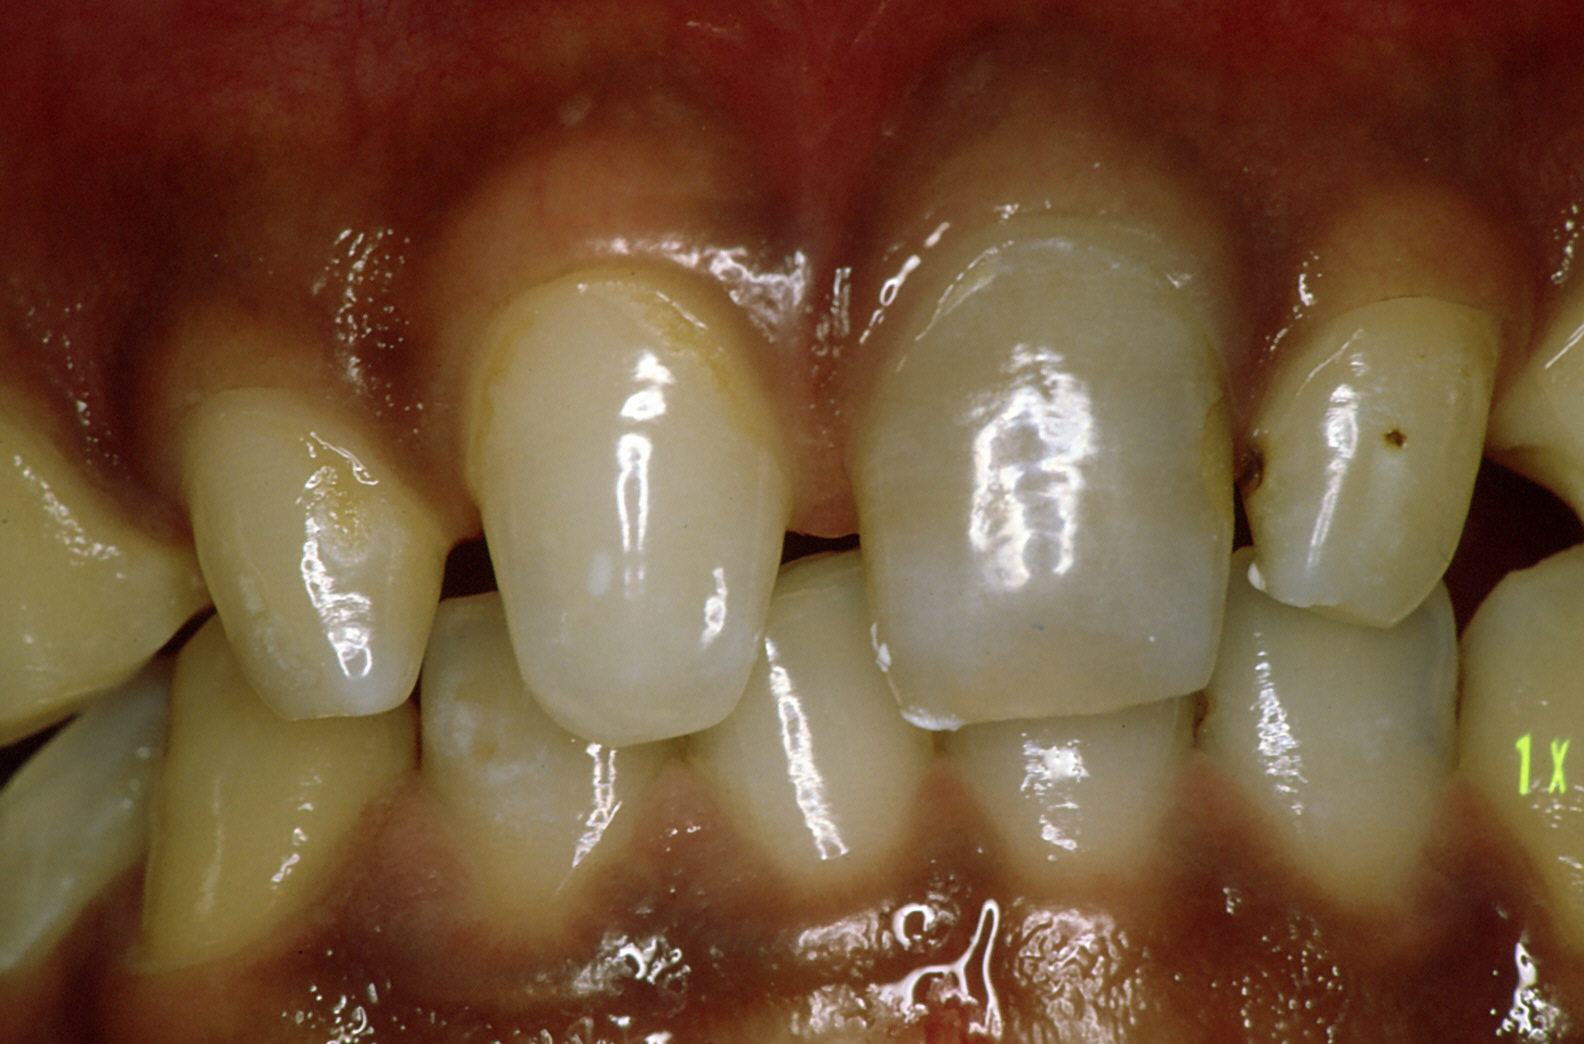

前歯の治療

「前歯は保険が効かない?」

こんな言葉昔は良く耳にしたのではないでしょうか。写真は同じ方です。保険で、それも歯はほとんど削っていません。

残念ながら欠点としては、変色すると言うことと、強度的に十分とはいえません。

金銭的な問題がクリアできる方は保険のきかないかぶせ物をお勧めします。変色の心配もなく、色合いはより歯に近くなり、強度も保険のものより高くなります。